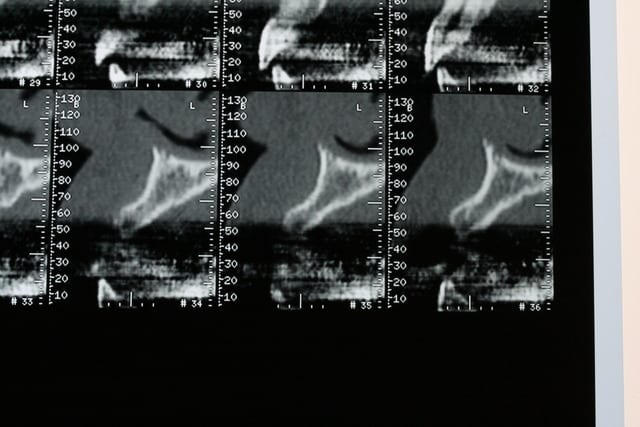

bon, première salve...

photos du scanner...et avec la planche radio pour bien estimer le volume disponible

d'entrée de jeu, on peut se dire que çà va être plus coton pour la 22 que pour la 12 car on à moins d'épaisseur et la corticale est plus dense...